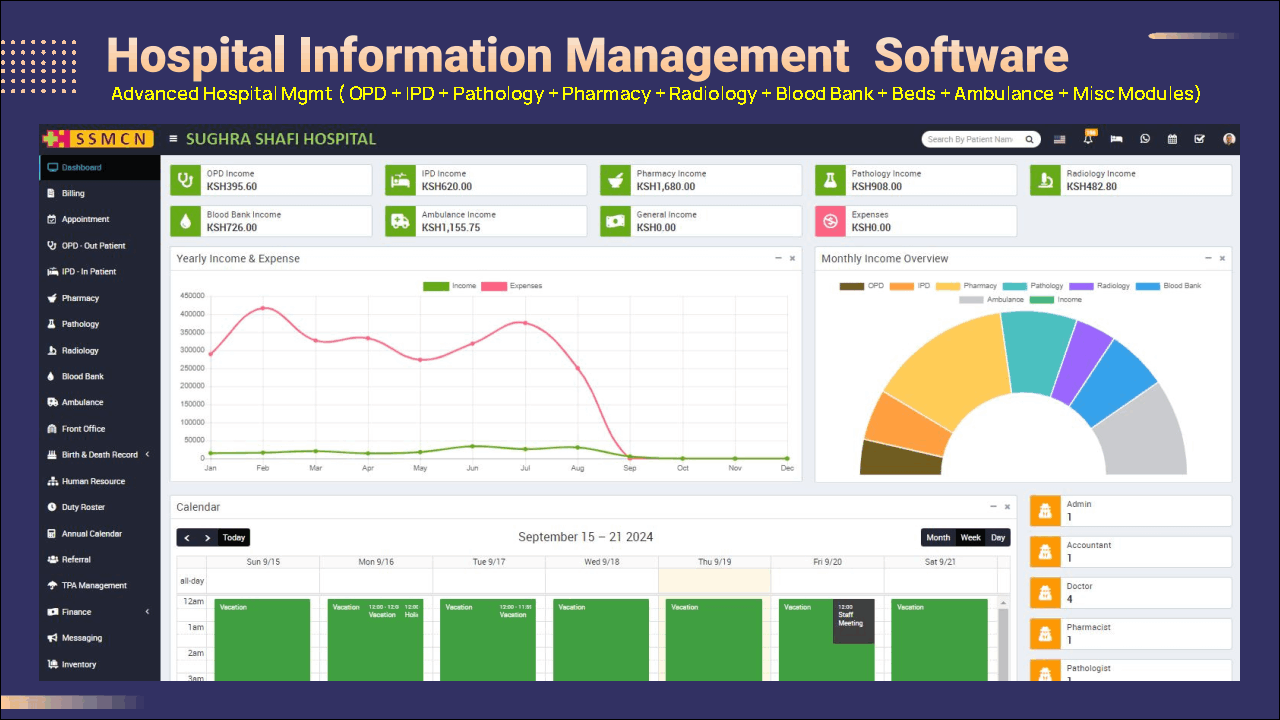

Hospital Information Management Software :

HIMS Modules :

Dashboard, Billing, Appointments, OPD (Out Patient), IPD (In Patient), Beds Management, Pharmacy Management, Pathology (Lab), Radiology, Blood Bank, Ambulance, Front Office, Birth & Death Record, Human Resource, Duty Roster, Annual Calendar, Referral, TPA Management, Finance Management, Messaging, Inventory, Staff / Patient ID Cards, Front CMS, Reports, Date filter added in Referral Report, Audit Trail Report, Patient Login, Credential Report, Inventory Item Reports, Pharmacy Refund Bill report, Discount in all modules, Barcode and QR code in both IPD or OPD Units, Company & Medicine Group page in Pharmacy, Antenatal Module in OPD/IPD

Vitals in IPD/OPD, Previous Obstetric History, Added Postnatal History, Patient Timeline, Prescription attachment in OPD/IPD.

Advance Optional

Live Consultation. Payment Gateways.

Tele-Health Module. Patient Portal.

Self Register Portal.

Customizations

(Optional)

- Custom UI.

- Custom Functionality

- Custom Branding.

- 3rd Party API Integs.